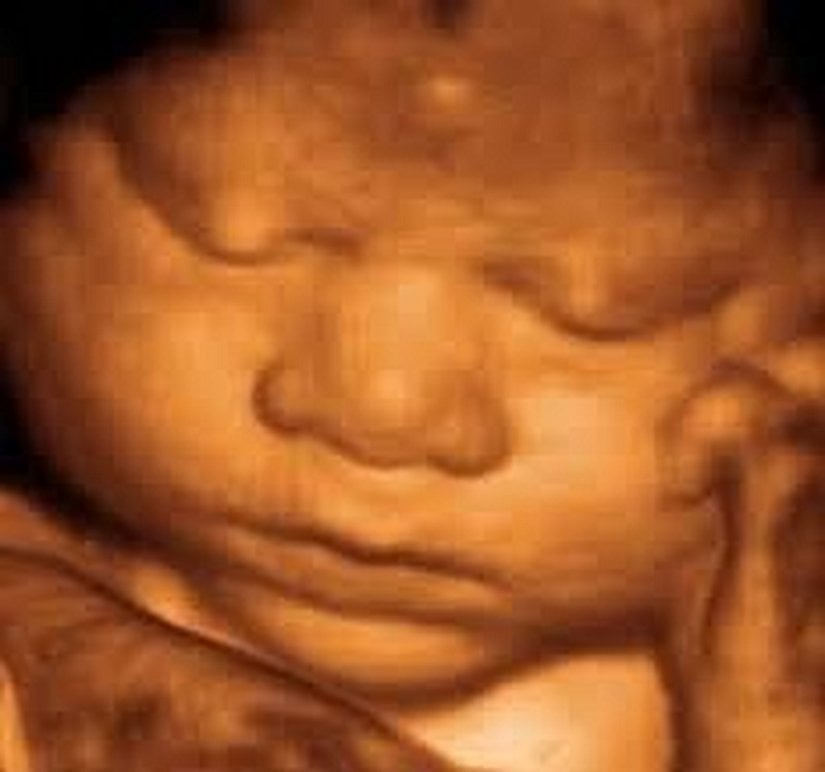

Ama giderek popülerleşen bir teknoloji sayesinde ebeveynler artık yavrularını çok daha net görebiliyorlar: 3D ve hatta 4D ultrason! Monako'daki Princes Grace Hastanesi'nde görev yapan Dr. Bernard Benoit, uzun yıllardır 3 boyutlu (ve hatta 4 boyutlu) ultrason görüntüleme teknikleri üzerinde çalışıyor ve çok başarılı sonuçlara da imza atmış vaziyette. Aşağıda, bunun bir örneğini görüyorsunuz.

Bu görüntüleme tekniği sayesinde, artık renkli ve çok daha net sonuçlara ulaşabiliyoruz. Bu görseller, bunun en net ispatlarından biri. Ana karnındaki ikizleri çok detaylı bir şekilde görüntülemek artık mümkün. Hem de o, uzaktan odaklanılmış bir kare. Aşağıdakiler, ne demek istediğimizi daha net anlatacaktır:

3D ultrasonlarda, birden fazla açıdan 2 boyutlu görüntüler çekiliyor ve sonrasında bilgisayar yardımıyla 3 boyutlu bir görsele dönüştürülüyor. Bu sayede bebeğinizin sadece bir kesidini değil, 3 boyutlu bir görüntüsünü elde etmeniz mümkün oluyor.

4D ultrasonlarda ise, 3D olan görüntüler zamana yayılmış bir şekilde kaydediliyor. Bu sayede bebeğin hareketlerini tıpkı bir video izler gibi görmeniz mümkün oluyor. Bu sayede bebeğin gözlerini açıp kapaması, gülümsemesi veya parmağını emmesi gibi olayları çok net bir şekilde görüntüleyebiliyorsunuz.